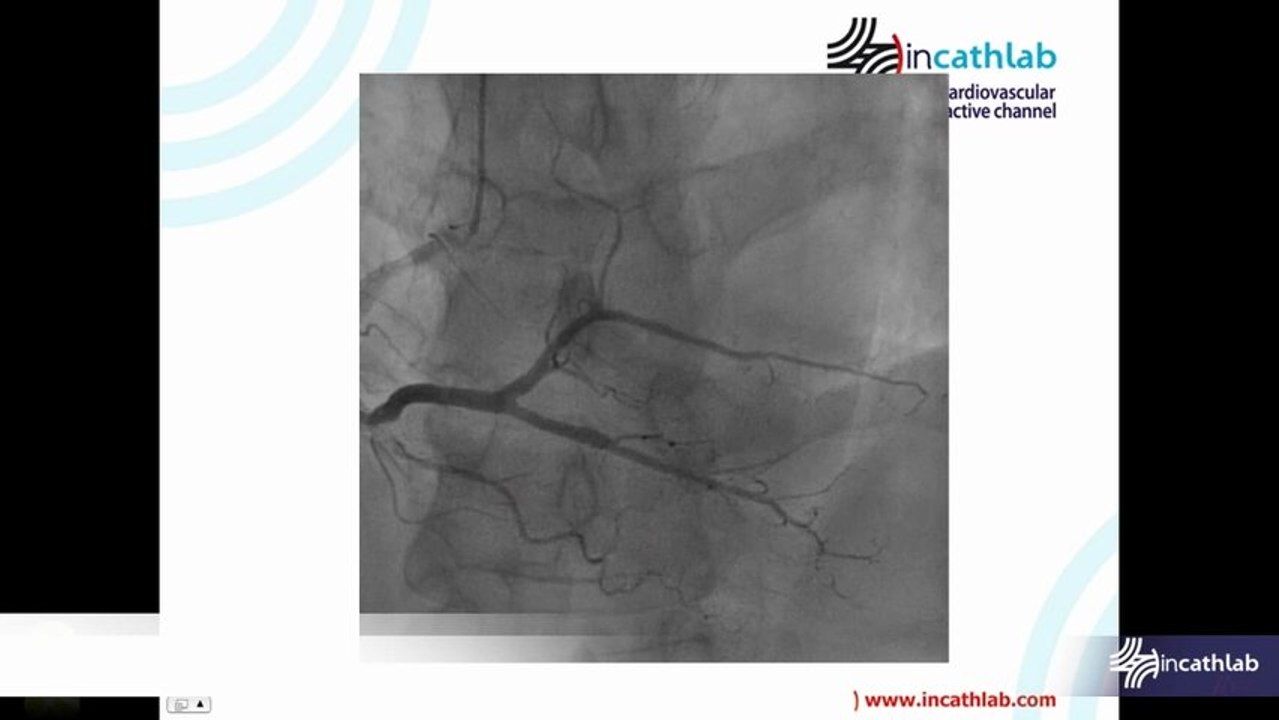

Mechanical Thrombectomy The better treatment option for acute to chronic PAOD ?

Rotarex presentation